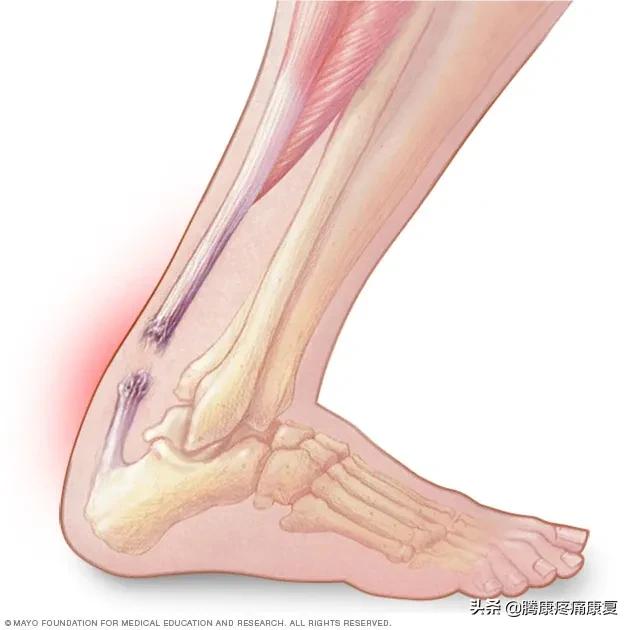

跟腱炎或断裂

跟腱是人体最大的肌腱,它位于腿部后侧,连接小腿肌肉和脚跟骨。

当肌腱受到刺激时,通常是由于过度使用,可能会感觉到腿后部的灼痛,通常就在脚跟上方。也可能有小腿疼痛和僵硬感,这就是众所周知的跟腱炎。

当跟腱肌腱撕裂时,腿后部可能会突然出现剧烈疼痛。腿可能很难承受任何重量。有些人在受伤时还会听到“砰”的一声。

跟腱炎分析与治疗预防